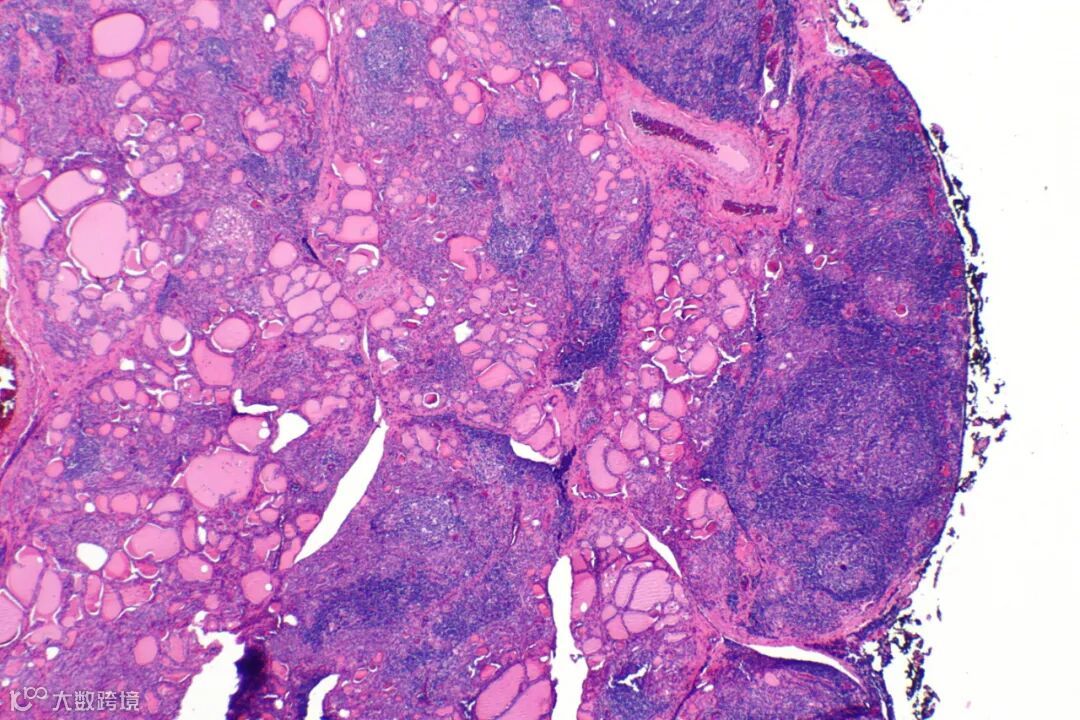

桥本氏甲状腺炎患者的甲状腺在低倍率显微镜下所呈现的影像 图源:wikipedia.org